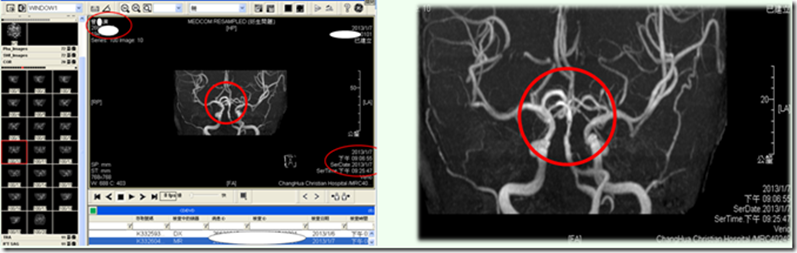

2013.01.07(一)血液、尿液检查,下午8:53pm医院安排进行MRI核磁共振,诊断确认为梗塞性脑中风。

MRI核磁共振影像显示,实体白色区段为血管堵塞处。

2013.01.07(一) 2013.01.10(四)

按推原始点前, 栓塞处清晰可见。 按推原始点后,栓塞处已消失。